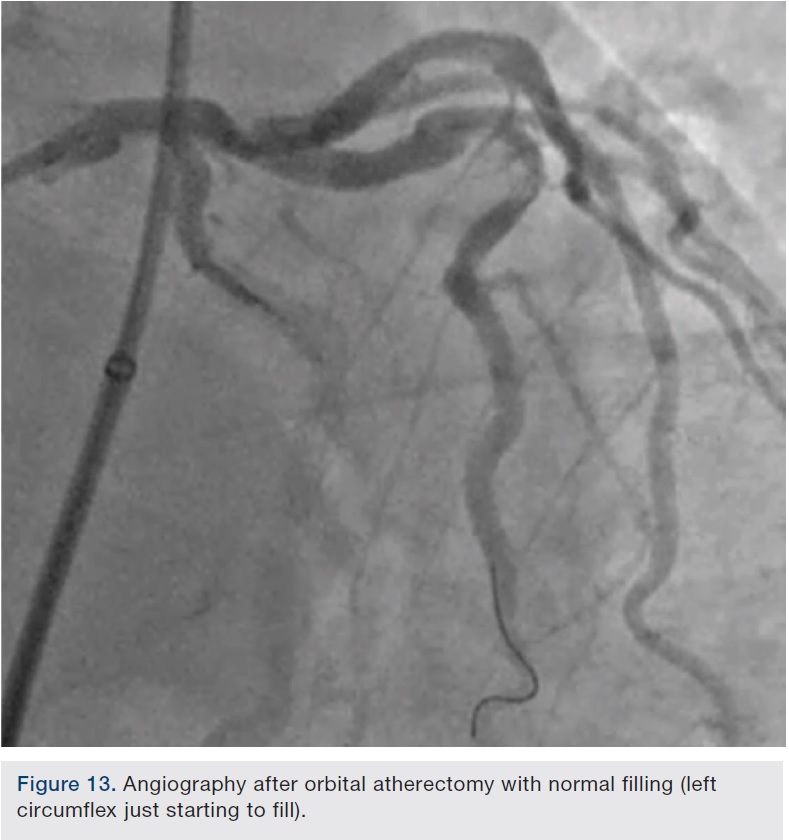

Preparation of this vessel was completed with atherectomy in order to facilitate stent delivery and optimal stent expansion. The Diamondback 360 orbital atherectomy system (CSI) was chosen, given the severe tortuosity. With the orbital device, there is a leading edge bushing ahead of the “working area” of the device, which prevents the wire from being cut on tortuous turns. A 1.25 mm device was used and was delivered around the most extreme portion of the tortuous vessel where the critical lesion was located. Several runs on low and high were performed (Figures 10-11). We then dilated the lesion with a 3.0 mm balloon, and angiography showed adequate balloon expansion (Figure 13). A GuideLiner (Vascular Solutions) was placed prior to stent delivery to increase chances of stent delivery, but also to decrease the chance of stent embolization if the stent had to be withdrawn. A 4.0 x 28 mm Promus Premiere stent (Boston Scientific) was then delivered fairly easily with good stent expansion (Figure 14) and the procedure was finished safely (Figure 15).